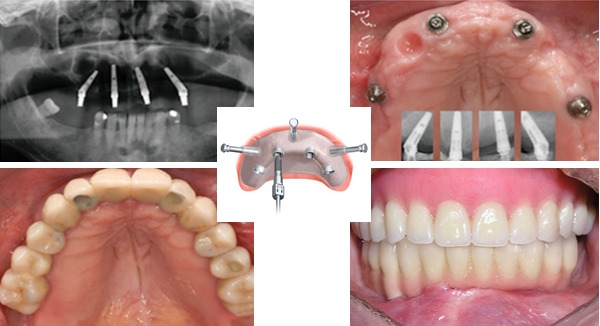

Trồng răng Implant cho người mất nhiều răng là giải pháp được chuyên gia đánh giá cao. Mang lại hiệu quả tốt hơn tất cả các phương pháp khác

So với hàm giả tháo lắp thì trồng răng Implant cho người mất nhiều răng là giải pháp được nhiều chuyên gia đánh giá cao hơn. Sau khi thực hiện kỹ thuật cấy ghép Implant, răng bị mất sẽ được phục hình toàn diện, đảm bảo cả về mặt thẩm mỹ lẫn hiệu quả ăn nhai.

Trồng răng Implant là kỹ thuật mà bác sĩ sẽ tiến hành cắm trụ Implant với số lượng thích hợp tùy vào từng trường hợp cụ thể, sau đó phục hình răng áp dụng cho

Hình minh họa trồng răng Implant giúp đảm bảo thẩm mỹ, chức năng ăn nhai, ngăn chặn tình trạng tiêu xương